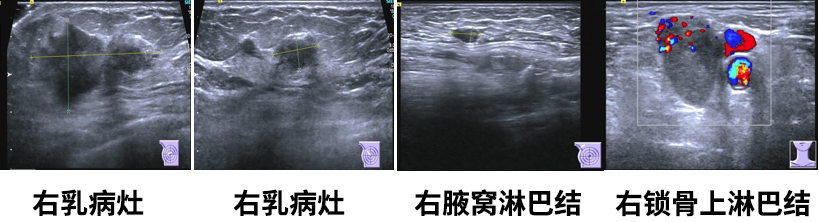

1.右乳肿物(约5.0*2.4*4.7cm),乳腺癌可能,BI-RADS5;

2.左乳切除术后,左胸壁未见明显异常;

3.右腋下(1.0*0.5cm)及右侧锁骨上淋巴结(2.6*1.8cm),转移可能。

乳腺MR

右侧乳头后侧中部多个异常信号结节(较大者23*15mm),符合乳腺癌,BIRADS:5类。右侧腋下肿大淋巴结,考虑转移。